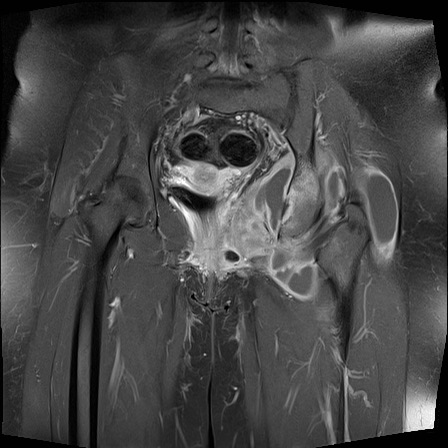

Hình ảnh X-quang khung chậu của bệnh nhân viêm khớp do lao tại khớp háng trái.

Có hẹp khe khớp kín đáo kèm theo xơ cứng dưới sụn tại khớp háng trái.

Các dấu hiệu X-quang này không đặc hiệu và rất có thể là biểu hiện của thoái hóa khớp.

Tiếp tục xem hình ảnh MRI…

Điều bất ngờ với tất cả mọi người là có nhiều ổ áp-xe.

Khi hình thành áp-xe lan rộng như vậy trong khi biểu hiện lâm sàng lại tối thiểu, cần luôn nghĩ đến viêm khớp do lao.

Chẩn đoán viêm khớp do lao được xác lập bằng chọc hút dịch khớp.